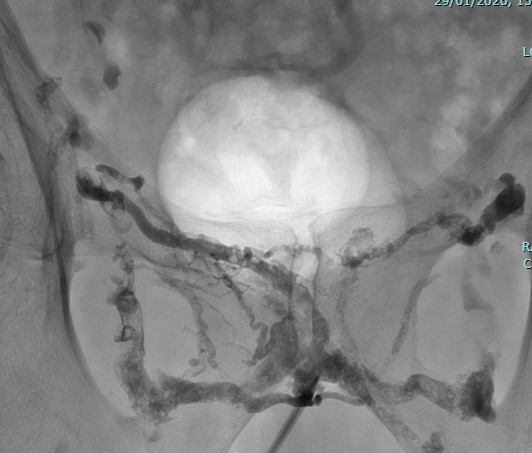

Angiographie :

Une imagerie des vaisseaux sanguins est réalisée pour localiser les rétrécissements ou la fuite sanguine.

En cas de fuite veineuse :

Embolisation de celle-ci : de la colle biologique est injectée pour boucher la fuite.